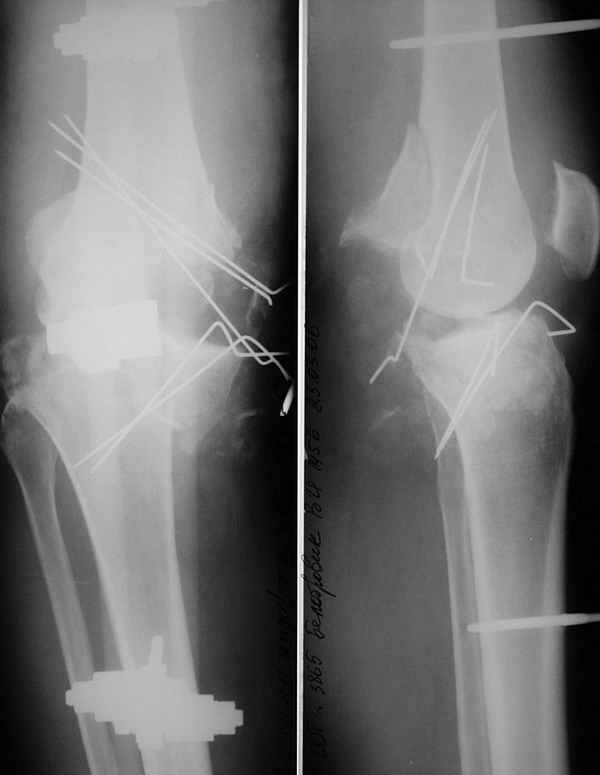

Больной 48 лет, соматически здоров, около 3 недель назад получил тяжелый открытый перелом внутренних мыщелков бедра и большеберцовой кости. Травма производственная - наехал бульдозер.

При поступлении - травматический шок 2 ст. При ревизии раны - отсутствие внутреннего мыщелка бедра, перелом внутреннего мыщелка б/б кости, нестабильность коленного сустава. Повреждений магистральных сосудов и нервов нет. Рваная лоскутная рана по внутренней поверхности колена. Выполнен адаптационный остесинтез остатков кости спицами и мостовидная трансартикулярная фиксация стержневым аппаратом внешней фиксации. Наводящие швы, частично - пластика по Хохутову. Сейчас раны заживают (местами с небольшими некрозиками, но в целом неплохо), встает вопрос о втором этапе лечения. Напрашивается вроде артродез коленного сустава.